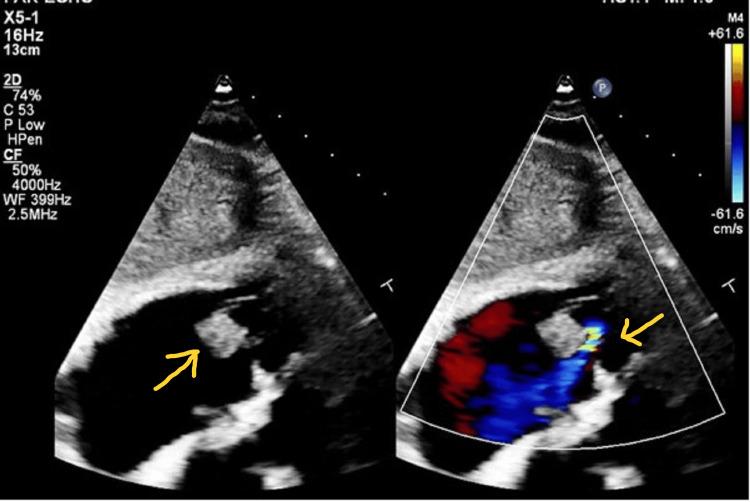

The incidence of infective endocarditis (IE) has been on the rise since it was first reported a century ago, and the associated mortality remains unchanged despite advances in medical and surgical management. To diagnose IE, the modified Duke criteria are used, which rely on isolating the causative organism. However, this can be challenging if the micro-organism is considered a contaminant. Staphylococcus lugdunensis (SL) is one such organism. In this case, an elderly female presented with intermittent chest pain, palpitation, and diaphoresis, for which she underwent left heart catheterization. Her hospital course was complicated by persistent fever and night sweats, leading to blood cultures isolating methicillin sensitivity. It was initially reported as a contaminant. However, an extensive workup was unremarkable, and a transthoracic echocardiogram was done, which revealed tricuspid vegetations with moderate regurgitation. The patient was treated with cefazolin, repeat cardiac imaging at the end of treatment revealed no vegetation, and the patient remained asymptomatic. Despite being associated with fulminant IE with higher mortality than Staphylococcus aureus (S. aureus), which requires surgical management in most cases, SL is still often reported as a contaminant. Isolation of SL should warrant further investigation beyond mere contaminants, and prompt treatment should be initiated in the appropriate clinical scenario to avoid poor outcomes.

自一个世纪前首次报道以来,感染性心内膜炎(IE)的发病率一直在上升,尽管在医学和外科治疗方面取得了进展,但其相关死亡率仍未改变。为了诊断IE,采用了改良的杜克标准,该标准依赖于分离致病微生物。然而,如果微生物被认为是污染物,这可能具有挑战性。路邓葡萄球菌(SL)就是这样一种微生物。在这个病例中,一位老年女性出现间歇性胸痛、心悸和多汗,为此她接受了左心导管检查。她的住院过程因持续发热和盗汗而复杂化,导致血培养分离出对甲氧西林敏感的菌株。最初它被报告为污染物。然而,全面检查未发现异常,并进行了经胸超声心动图检查,结果显示三尖瓣有赘生物并伴有中度反流。患者接受了头孢唑林治疗,治疗结束时重复心脏成像显示没有赘生物,患者仍无症状。尽管SL与暴发性IE相关,其死亡率高于金黄色葡萄球菌(S. aureus),在大多数情况下需要手术治疗,但SL仍经常被报告为污染物。分离出SL应保证除了单纯作为污染物之外进行进一步调查,并且在适当的临床情况下应立即开始治疗,以避免不良后果。